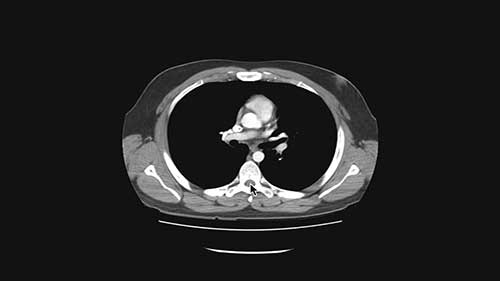

大脑低剂量CT扫描